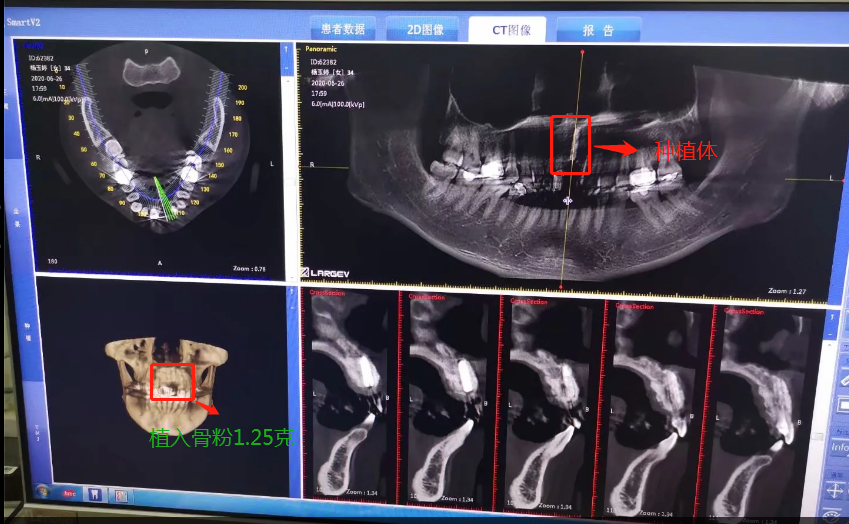

2020年6月26日,終于等到了,我要種植了牙根啦,我牙根弄了法國安卓建品牌的種植體,之前還去幾家口腔門診和烈士陵園的光華口腔也咨詢過和對(duì)比價(jià)格,瑞士ITI品牌太貴了(還有別的品牌M美國皓圣、韓國登騰、德國ICX、瑞典諾貝爾等),本來選美國皓圣,但我的是門牙,要選材質(zhì)比較好,考慮美觀問題,后選擇中等價(jià)位的安卓健。手術(shù)很快,而且傷口不是很大,我四天就康復(fù),做完當(dāng)下就可以說話,完全沒有阻礙。因?yàn)檠栏N進(jìn)去必須要等半年時(shí)間跟我骨頭長在一起,因?yàn)槲耶?dāng)時(shí)做手術(shù)的時(shí)候種植入的骨粉還是軟的,還沒有變成硬骨頭?,F(xiàn)在的階段是等待上基臺(tái),上完基臺(tái)半個(gè)月時(shí)間上牙冠。2020年12月26日上基臺(tái)。預(yù)計(jì)要2021年1月份可以全部完成種牙過程,期待著我?guī)涎例X的那一刻。

植入種植體后拍的CT

種植骨粉及種植體的記錄